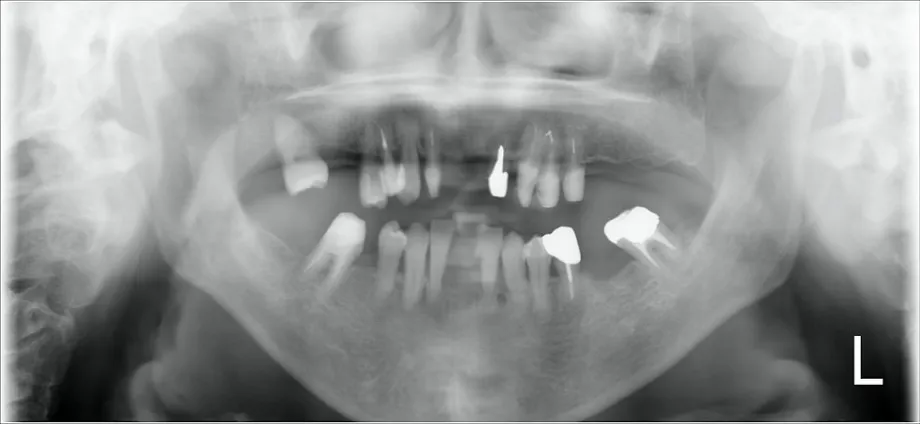

1審査診断

お口の写真やレントゲン、歯周病検査など、必要な資料をとり、治療の計画をたてます。